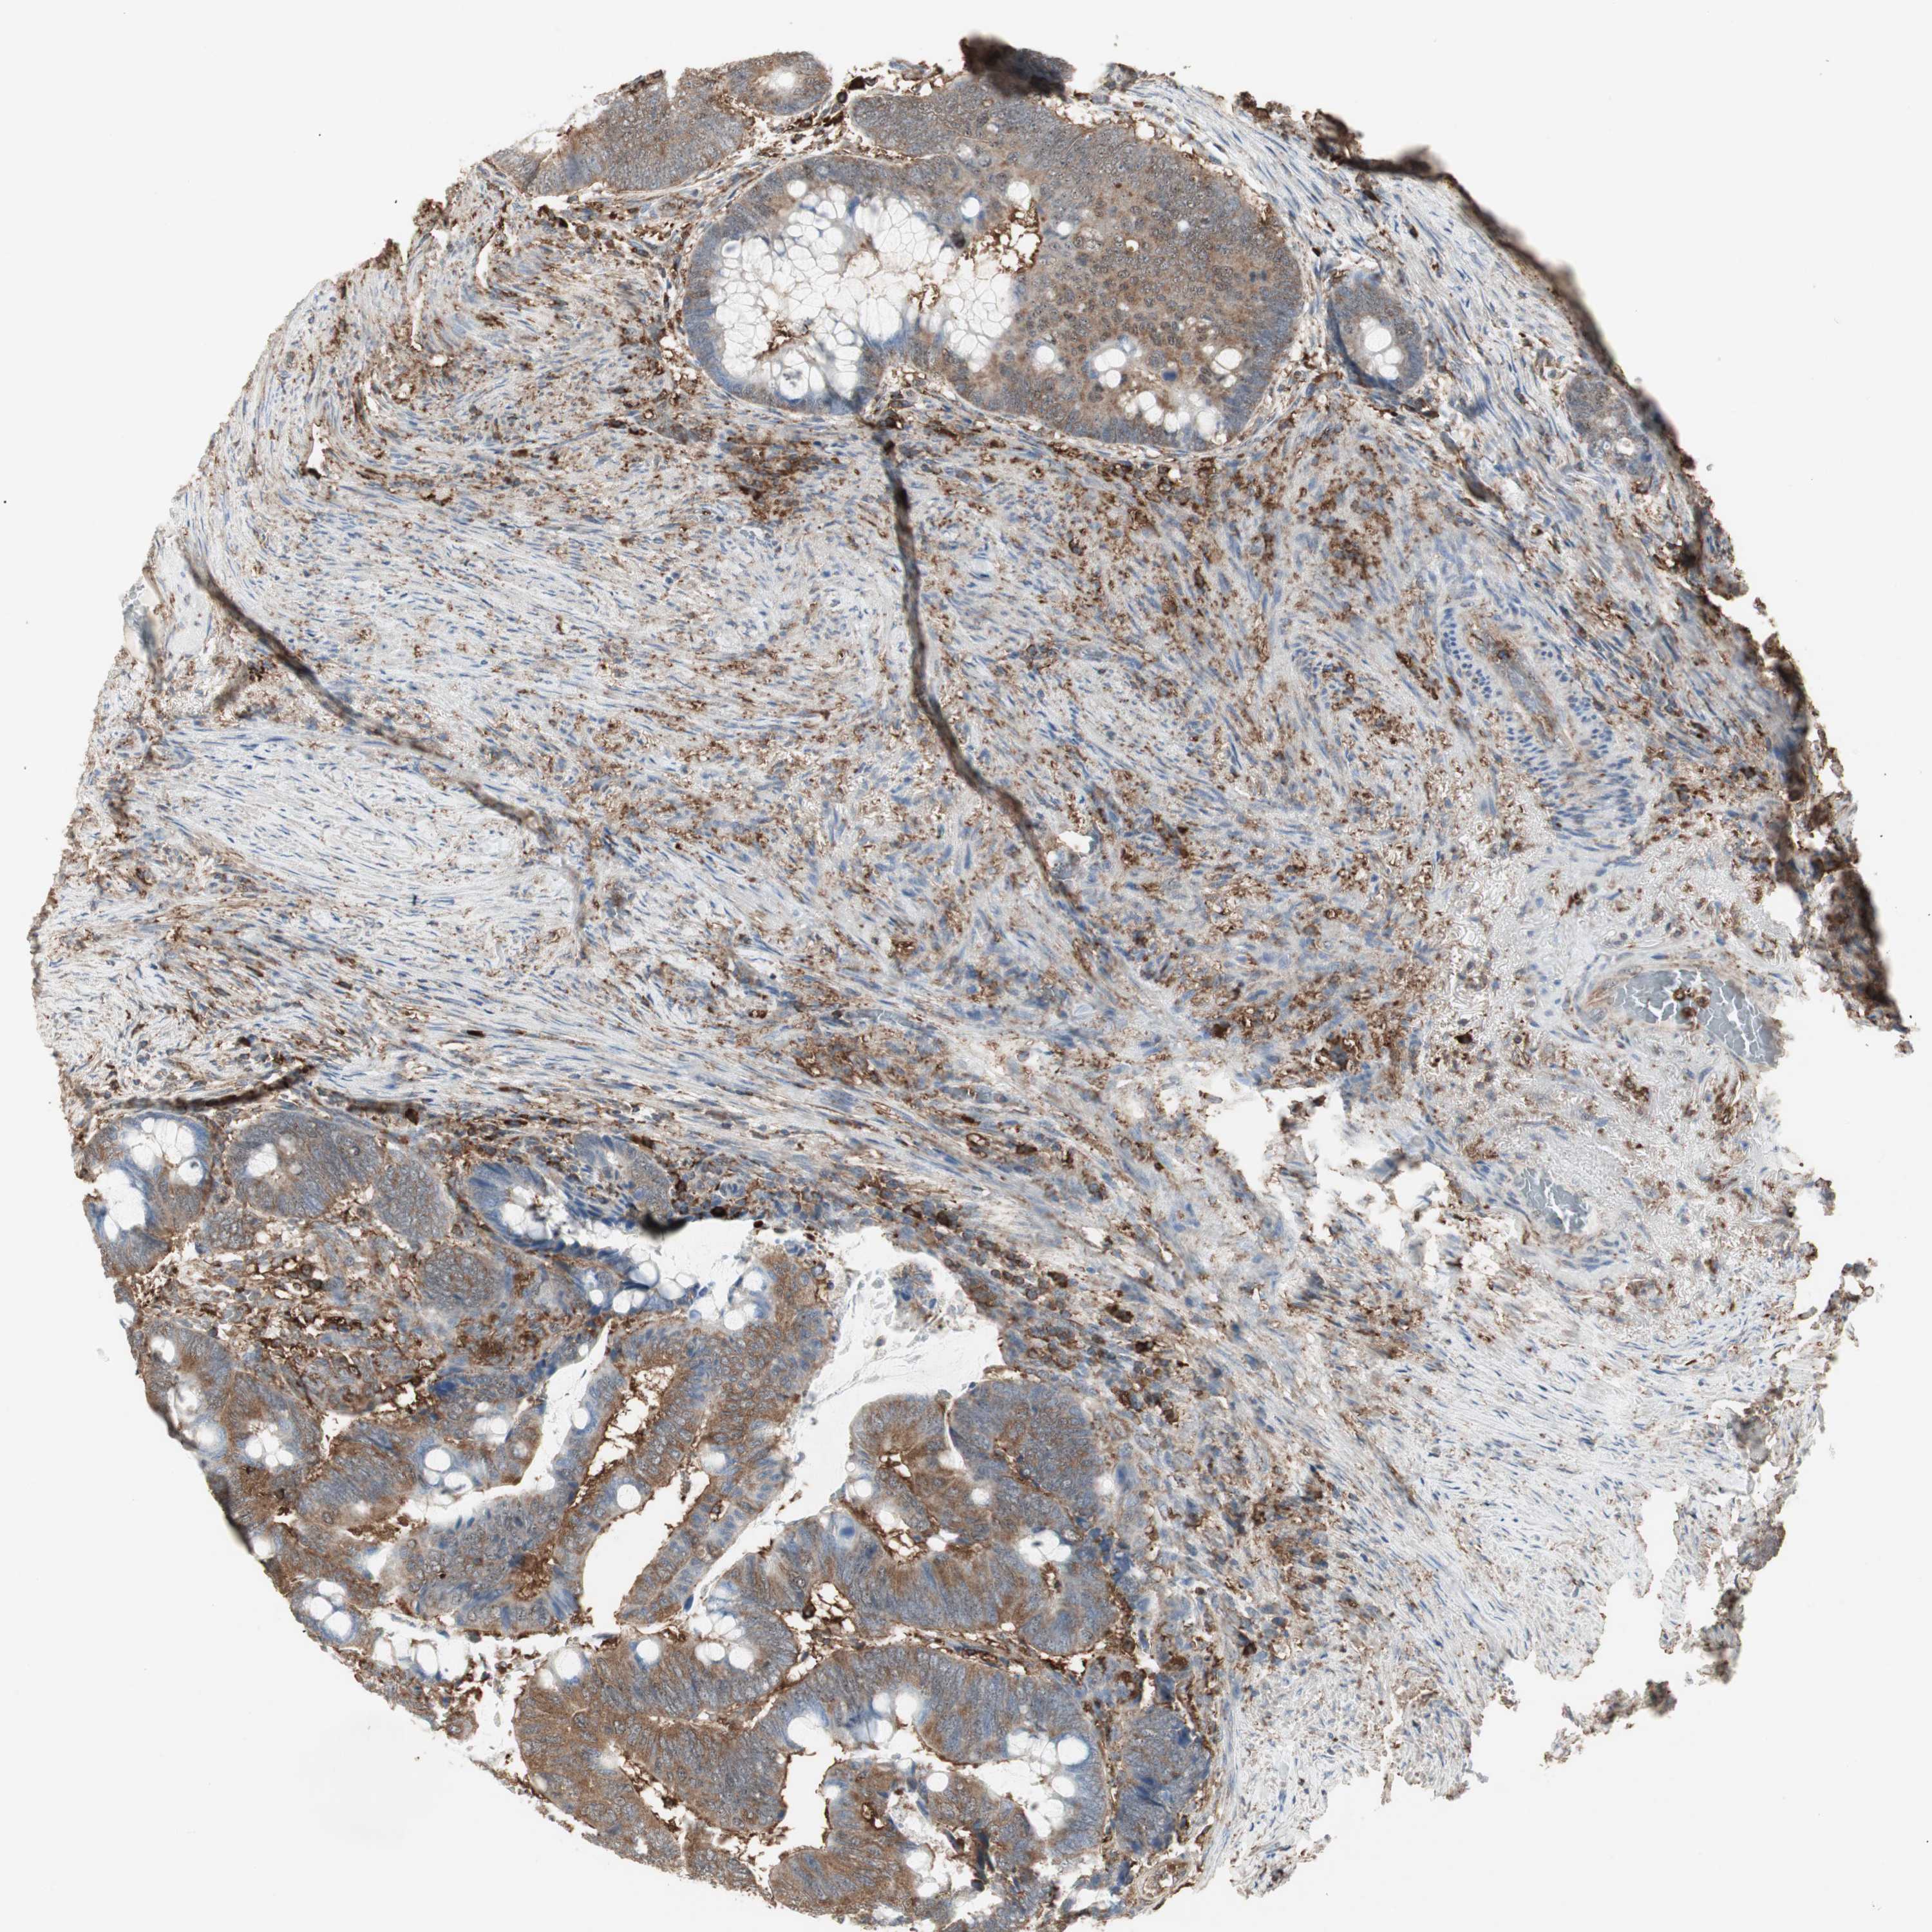

RECTUM ADENOCARCINOMA (TCGA) - Interactive survival scatter ploti

The Survival Scatter plot shows the clinical status (i.e. dead or alive) for all individuals in the patient cohort, based on the same data that underlies the corresponding Kaplan-Meier plots. Patients that are alive at last time for follow-up are shown in blue and patients who have died during the study are shown in red.

The x-axis shows the expression levels (FPKM) of the investigated gene in the tumor tissue at the time of diagnosis. The y-axis shows the follow-up time after diagnosis (years). Both axes are complimented with kernel density curves demonstrating the data density over the axes. The top density plot shows the expression levels (FPKM) distribution among dead (red) and alive patients (blue). The right density plot shows the data density of the survived years of dead patients with high and low expression levels respectively, stratified using the cutoff indicated by the vertical dashed line through the Survival Scatter plot. This cutoff is automatically defined based on the FPKM cutoff that minimizes the p-score. The cutoff can be changed by dragging the vertical line or by entering a cutoff value in the square labeled "Current cut-off".

Under the Survival Scatter plot the p-score landscape (black curve; left axis) is shown together with dead median separation (red curve; right axis). Dead median separation is the difference in median mRNA expression between patients who have died with high and low expression, respectively. It is calculated as follows: median FPKM expression of dead patients with high expression - median FPKM expression of dead patients with low expression. This is intended to aid the user in visually exploring custom cutoffs and the associated p-scores and dead median separation.

Individual patient data is displayed and can be filtered by clicking on one or more of the category buttons on the top of the page. Categories describing expression level and patient information include: high, low, alive, dead, female, male and tumor stages. The scale of the x-axis can be toggled between linear and log-scale by clicking on the "x log" button. Mouse-over function shows TCGA ID, patient information and mRNA expression (FPKM) for each patient.

& Survival analysisi

Kaplan-Meier plots summarize results from analysis of correlation between mRNA expression level and patient survival. Patients were divided based on level of expression into one of the two groups "low" (under cut off) or "high" (over cut off). X-axis shows time for survival (years) and y-axis shows the probability of survival, where 1.0 corresponds to 100 percent.

MMP3 is not prognostic in Rectum Adenocarcinoma (TCGA)

Best expression cut offi

Based on the FPKM value of each gene, patients were classified into two groups and association between prognosis (survival) and gene expression (FPKM) was examined. The best expression cut-off refers the FPKM value that yields maximal difference with regard to survival between the two groups at the lowest log-rank P-value. Best expression cut-off was selected based on survival analysis .

When clicking on this number, the vertical dashed line indicating cut-off, the interactive survival plot, and the Kaplan-Meier curve will be adjusted to show results based on the best expression cut-off.

: 36.39

P scorei

Log-rank P value for Kaplan-Meier plot showing results from analysis of correlation between mRNA expression level and patient survival.

N/A

5-year survival highi

5-year survival for patients with higher expression than the expression cutoff.

For melanoma and glioma, 3-year survival is shown.

5-year survival lowi

5-year survival for patients with lower expression than the expression cutoff.

TCGA RNA samplesi

RNA-seq data is reported as average FPKM (number Fragments Per Kilobase of exon per Million reads), generated by the The Cancer Genome Atlas (TCGA) .

Normal distribution across the dataset is visualized with box plots, shown as median and 25th and 75th percentiles. Points are displayed as outliers if they are above or below 1.5 times the interquartile range. FPKM values of the individual samples are presented next to the box plot.

Average pTPM 54.3

Number of samples 88